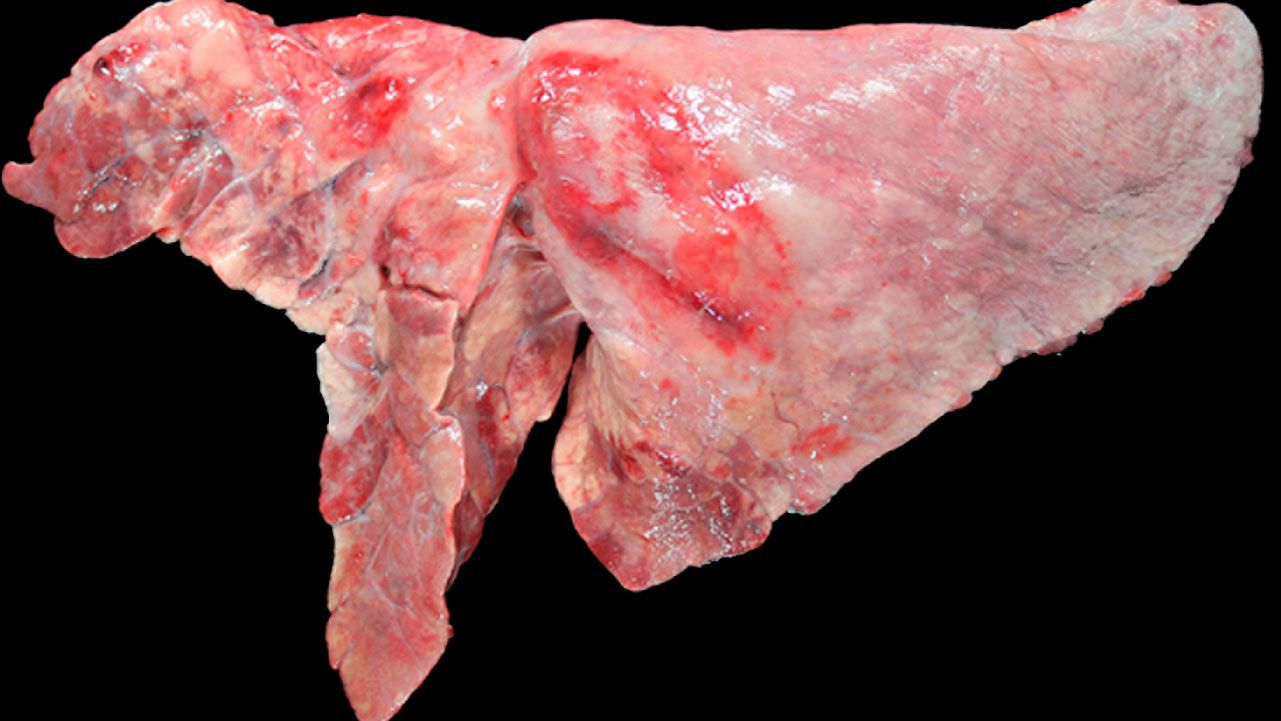

Treatment and control is not simple since enzootic pneumonia is a multi-factorial disease. Chronic pneumonia of swine has been recognized as a serious impediment to swine production for almost 100 years 27. Macroscopically the lungs do not collapse when removed from the thoracic cavity presenting a rubbery consistency and multifocal patchy areas of redness distributed throughout the lung parenchyma Figure 1.

Lungs From A Three Week Old Pig Severe Diffuse Proliferative Download Scientific Diagram